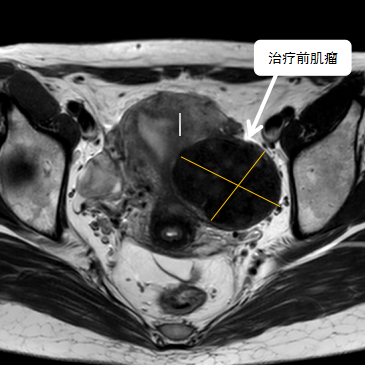

術(shù)前影像資料

經(jīng)過(guò)兩個(gè)月的藥物預(yù)處理,完善術(shù)前準(zhǔn)備,治療當(dāng)天陳主任帶領(lǐng)團(tuán)隊(duì)在3.0T磁共振清晰圖像引導(dǎo)下對(duì)子宮肌瘤進(jìn)行精準(zhǔn)消融,患者全程清醒,沒(méi)有明顯疼痛,經(jīng)過(guò)1個(gè)多小時(shí)的精細(xì)操作,手術(shù)非常成功,消融率接近90%,內(nèi)膜未見(jiàn)損傷!觀察一個(gè)小時(shí)后患者即自行回家。

術(shù)后即刻行增強(qiáng)磁共振檢查,顯示病變被消融近90%,內(nèi)膜未見(jiàn)損傷